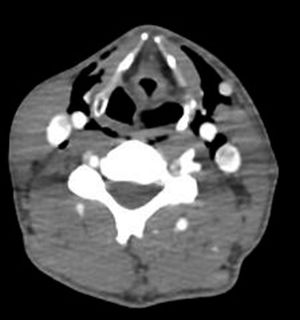

A 39-year-old man was admitted to the emergency room in our hospital after a car accident. No previous diseases were known. There was no loss of consciousness, no nausea or vomiting, and he remained hemodynamically stable during his stay in the emergency room. Upon examination, respiratory and cardiac auscultation was normal, however palpitations revealed that the patient had pain in the right antero-superior iliac spine and right rib, as well as ptosis and miosis of the left eye, without apparent anhidrosis (fig. 1). There were neither latero-cervical murmurs nor subcutaneous emphysema found during the physical exam, and the rest of the neurological examination was without clinically relevant findings. A protocol CT total body scan revealed cervical emphysema, pneumomediastinum, pulmonary contusion and splenic laceration. A CT angiography of the neck was specially requested, showing bilateral latero-cervical emphysema with no dissection of the carotid or vertebral arteries (fig. 2). Given the results, we performed a neurosonological study with an ecodoppler that showed no intimal flap, although it showed hipoecogenic bubbles surrounding the left carotid artery. Conservative treatment was pursued related to the neurologic findings and after one year the patient improved to full recovery of the symptoms.